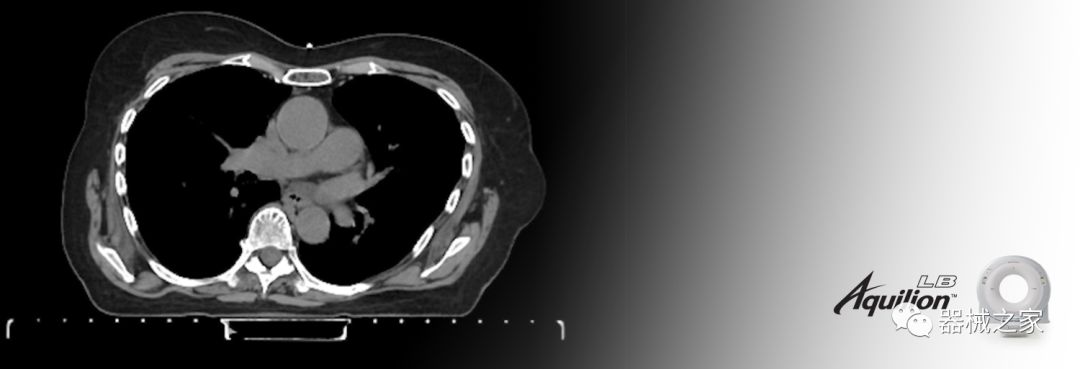

擴展視野(EFOV)可以看到更多的解剖結構。Aquilion LB采用85 cm EFOV,而Aquilion Prime SP和Aquilion Lightning 70采用70 cm EFOV。

Aquilion LB專為滿足腫瘤學挑戰(zhàn)而設計,同時優(yōu)先考慮患者護理。Aquilion LB的內徑為90 cm,能夠幫助復雜的患者設置并提高患者的舒適度。CT模擬定位可以輕松鏡像放射治療定位,更加自信。該系統(tǒng)采用0.5 mm x 16排(32層)PUREViSION探測器技術,70 cm視野,AIDR 3D和SEMAR技術。